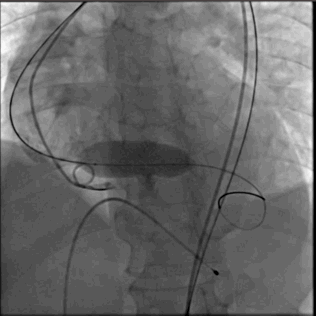

输送系统到位

圈套器snare 协助输送系统安全准确达到预计区域,猪尾主动脉根部造影确认系统和窦底的相对位置,调整重置锚定区

瓣膜释放

VenusA 26支架,高位 释放

1.ring释放到mark点往下2mm处,造影观察位置(此时仍可以调整位置)